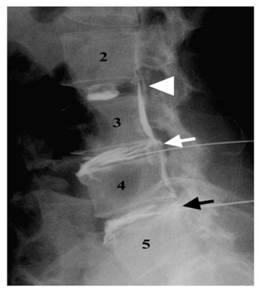

Figure 5

Lateral discograms show a type 2 lobular pattern at L2-L3 (arrowhead), a type 5 ruptured pattern at L3-L4 (white arrow), and a type 4 fissured pattern at L4-L5 (black arrow). The patient was painless at L2-L3 and had concordant pain at L3-L4 and L4-L5 during discography. (Adopted from Chae-Hun Lim, et al. [47]).